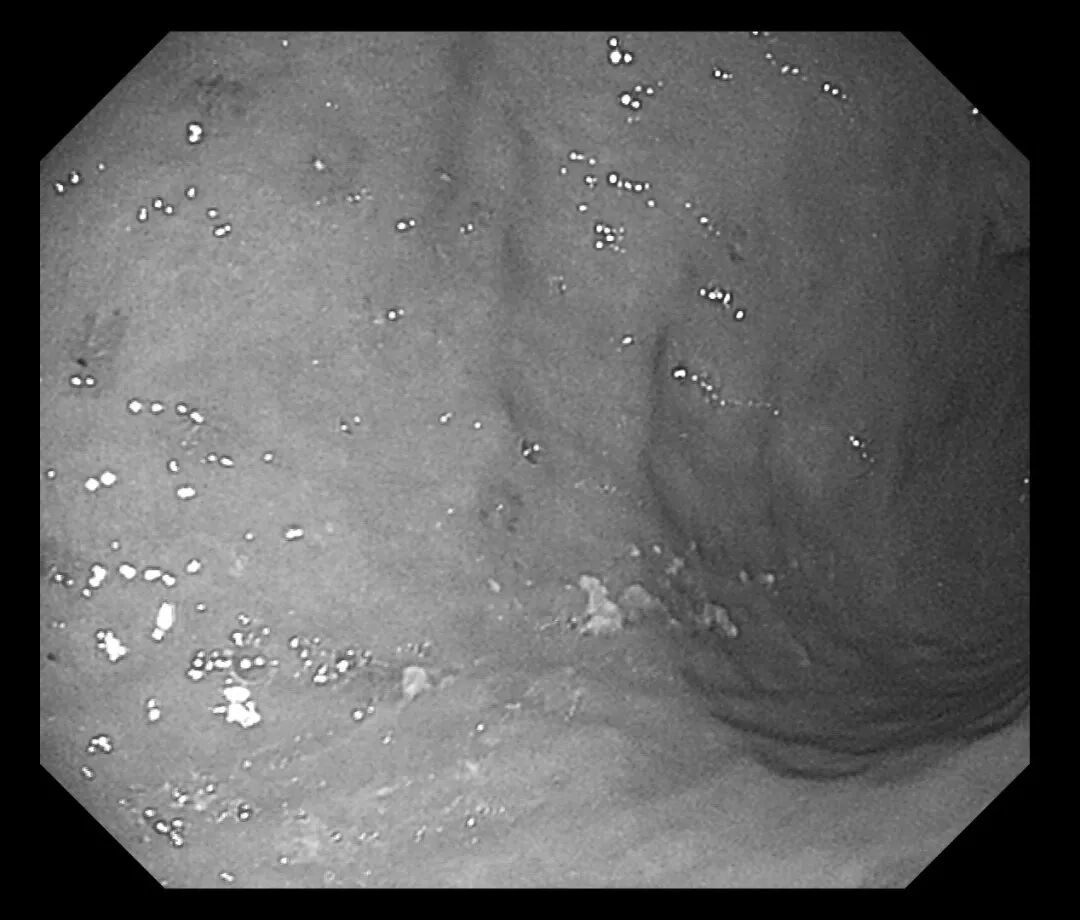

接诊医生刘润萍详细询问病史后,敏锐地意识到这可能是一例典型的“药物性胃溃疡”病例。为明确诊断,在评估患者情况后为其安排胃镜检查。检查结果令人大为震惊:胃窦、胃体等多处黏膜可见十余个直径0.3-0.5cm不等的溃疡灶,部分表面覆有白苔,周围黏膜充血水肿明显。结合患者近期用药史,考虑为“非甾体抗炎药相关性胃溃疡”。

(胃体溃疡)